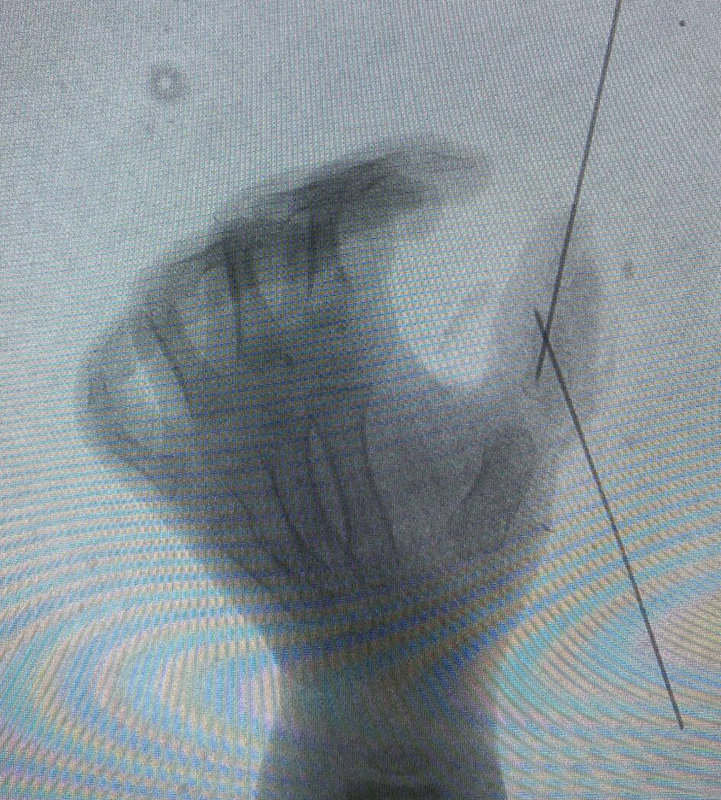

多指術(shù)后鋼針多長時間拔除

鋼針多在術(shù)后4-6周拔除!很多多指手術(shù)需要做相關(guān)掌骨、指骨截骨以糾正偏斜畸形,截骨后需要用一根或者多根像“繡花針”一樣粗細(xì)的克氏針做臨時固定。截骨的骨端多在術(shù)后4-6周長好,再通過復(fù)查x片,確定截骨端骨頭愈合了,就可以在門診拔除克氏針了,拔除克氏針基本沒有什么疼痛,家長們不用擔(dān)心小寶寶受太多苦了!拔除鋼針后,就要開始手指的功能鍛煉啦!

“寶寶多指一定要插釘子嗎?”這句話我在門診經(jīng)常會聽到,很多寶爸寶媽一看到克氏針,第一反應(yīng)就是寶寶很疼,所以會問能不能不打,為什么非得打。首先,并不是所有類型的多指在手術(shù)之后都要打克氏針,有些之所以會打,是為了給寶寶術(shù)后的恢復(fù)提供比較好的環(huán)境。我們手術(shù)用來修補(bǔ)的縫線比頭發(fā)絲還細(xì),雖然縫線有一定的張力和強(qiáng)度,但如果寶寶的手動的比較劇烈,那么縫線一定會被扯斷。為了避免術(shù)后出現(xiàn)意外扯斷等情況,給寶寶手指一個比較好的內(nèi)固定是很有必要的。對于做了截骨矯形的寶寶來說,更需要內(nèi)固定輔助。多指類型不同,內(nèi)固定的拆除時間也不一樣。如果是為了防止軟組織出現(xiàn)撕脫,一般3-4周拆除內(nèi)固定。如果是為了固定骨組織,一般6周進(jìn)行拆除。

回答:一般建議一歲半左右手術(shù)多指手術(shù)并沒有最佳手術(shù)年齡,特別輕的多指,類似小皮贅的畸形,多指與正常拇指沒有形成關(guān)節(jié)或骨性相連,只是皮膚和軟組織連著,只要孩子能耐受麻醉,幾個月大就可以手術(shù)!但是考慮到麻醉風(fēng)險,多建議一歲后手術(shù)!而對于復(fù)雜多指畸形,多指與正常(保留)手指有骨性連接,切除多指后,保留拇指還需要做截骨矯形,糾正拇指歪斜,并用鋼針臨時內(nèi)固定的患兒,因此多建議一歲半后再手術(shù)!因為這個時候,孩子的骨頭才有一定的硬度,能經(jīng)得住鋼針的固定!年齡越大,骨頭越硬,越能吃得住鋼針,但是多指手術(shù)并不能一味往年齡大了拖,因為科學(xué)研究證實,手腦訓(xùn)練的最佳年齡是2歲半前,因此,多建議在此年齡段前手術(shù)!